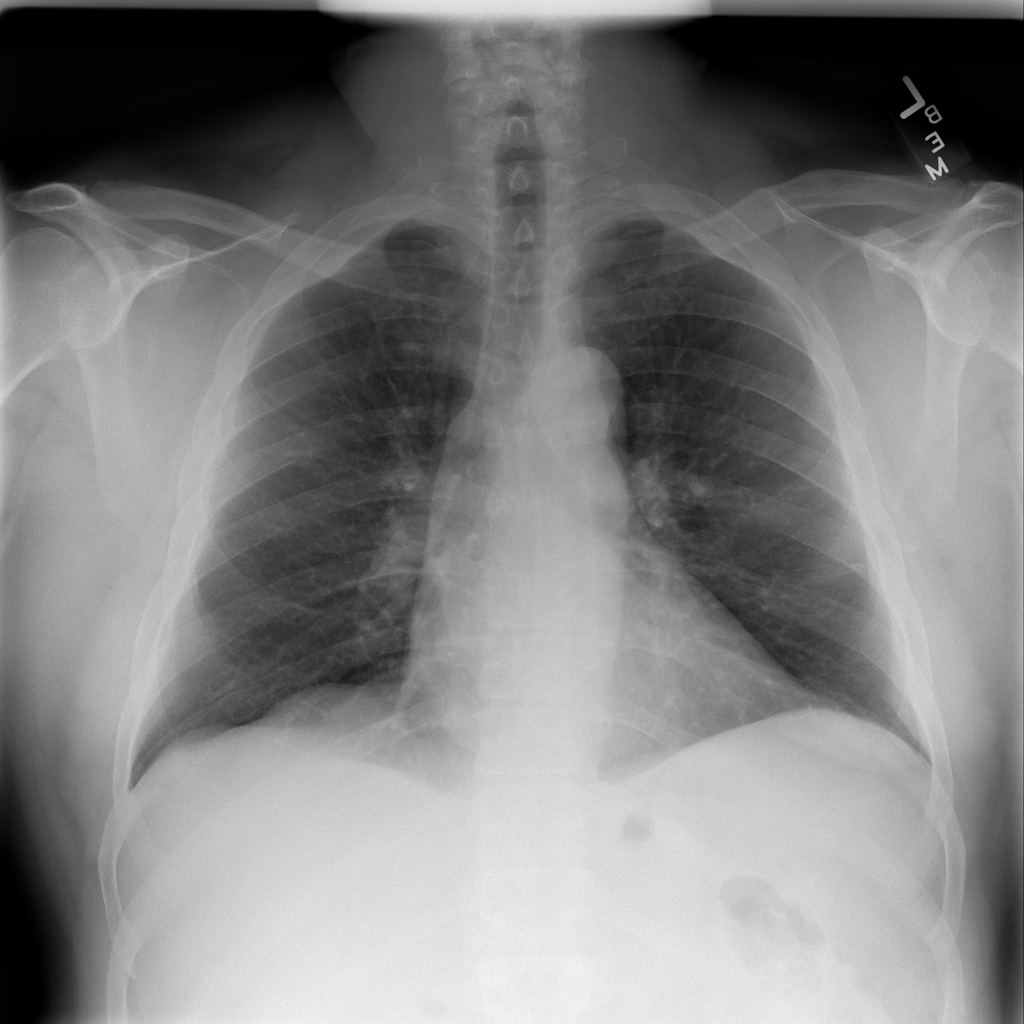

PAT-E828 · IMG-004Edema

PAT-E828 · IMG-004

AP